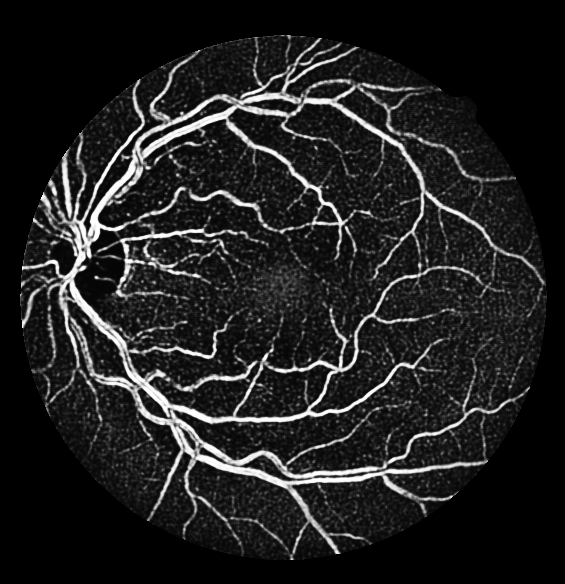

The evaluation of each experiment over the five different initialization roll-outs are reported in Table 1-4. The mean and standard deviations of five commonly used metrics, namely specificity, sensitivity, F1 score, accuracy and the AUC score are presented. The threshold for binarization is selected such that the F1 score is maximized on the validation sets. The threshold independent AUC score is chosen as the main performance indicator. The output probability maps of the degenerated trials are presented in Fig. 2 (c-f).

Table 1 shows that the AUC scores of additive U-Net variants fluctuate merely on the fourth digit, meaning that the expected performance boost is missing. The reduced number of convolutional layers in each level impairs the network marginally, while the absence of non-linearity has an impact on the performance. As for the subtractive experiment series with decreasing numbers of network levels in Table 2 and initial filters in Table 3, surprisingly not until the U-Net contains only one level and collapses into a sequence of convolution layers, or the number of initial filters drops to one, the segmentation results remain satisfactory with an AUC score above 0.97. In respective of the generalization study as reported in Table 4, a monotonous AUC score decline is observed with reducing amount of training subsets, in accordance with our prediction. However we did not anticipate that two sets for training already achieves an AUC score above 0.96, which indicates that the default U-Net has a high generalization capability in retinal vessel segmentation on DRIVE database.